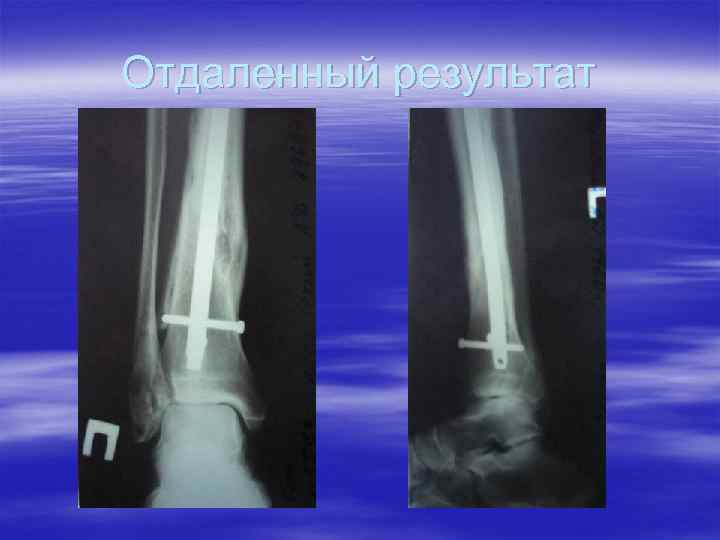

Остеосинтез переломов б/б кости типа В 2 в н/3

Отдаленный результат